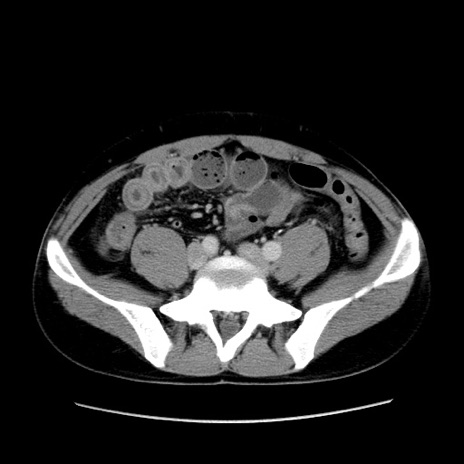

症例4(横断像)

【症例】30歳代男性

【主訴】腹痛、嘔吐

【現病歴】昨晩から突然の腹痛あり、その後嘔吐、軟便も出現。腹痛が改善しないため救急搬送となる。2日前にしめ鯖の食事歴あり。

【身体所見】意識清明、苦悶様、BP 135/90mmHg、BT 35.7℃、腹部:平坦、やや硬、心窩部〜臍部に自発痛、圧痛あり、筋性防御+、反跳痛-

【データ】WBC 8100、CRP 0.57